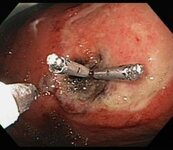

Large gastric ulcer after the endoscopic placement of two mechanical clips to provide haemostasis and prevent rebleeding

From the collection of Douglas G. Adler, MD